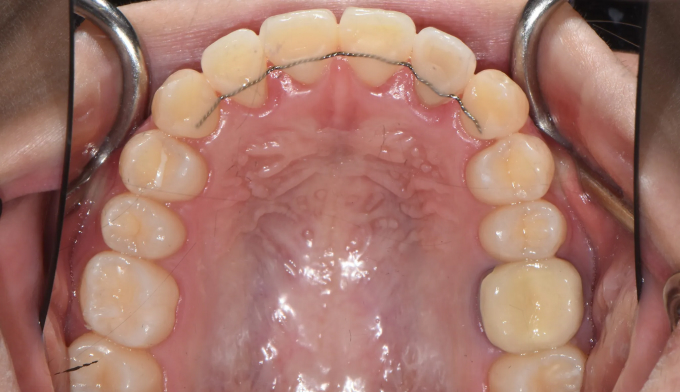

최대한 좁은 악궁을 확장하고 부족하면 전체 치열의 후방이동을 통하여 덧니를 배열할 공간을 만들었습니다.

총 치료기간은 25개월 입니다.

입술의 두께나 입매의 변화 없이 치열만 고르게 배열하였습니다.